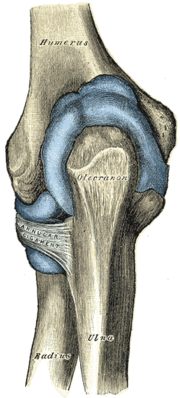

![]() Left elbow-joint, showing anterior and ulnar collateral ligaments. | |

المرفق إنگليزية: Elbow هي عظمة مفصلية تربط عظمة العضد مع عظمتي الزند و الكعبرة. وتكون أماكن الالتقاء الثلاثة، ثلاثة مفاصل أصغر وتسمح هذه المفاصل الصغيرة بحركات معينة، حيث يسمح مفصلا العضد ـ الزند والعضد ـ الكعبرة للشخص بثني الساعد إلى أعلى وأسفل، بينما يسمح مفصلا الكعبرة ـ الزند والعضد ـ الكعبرة بدوران الساعد وكذلك راحة اليد أعلى وأسفل.

يحيط بمفصل الكوع كبسولة من نسيج متين. وتقوم هذه الكبسولة مع عدد من الأنسجة القوية الحبلية الشكل التي تُعرف بالأربطة بالمحافظة على العظام في أماكنها. ويعمل السائل الزيلي بمثابة مزلق لتقليل الاحتكاك عند الكوع.

| Joint | From | To | Description |

| humeroulnar joint | trochlear notch of the ulna | trochlea of humerus | Is a simple hinge-joint, and allows of movements of flexion and extension only. |

| humeroradial joint | head of the radius | capitulum of the humerus | Is a hinge-joint joint. |

| proximal radioulnar joint | head of the radius | radial notch of the ulna | In any position of flexion or extension, the radius, carrying the hand with it, can be rotated in it. This movement includes pronation and supination. |